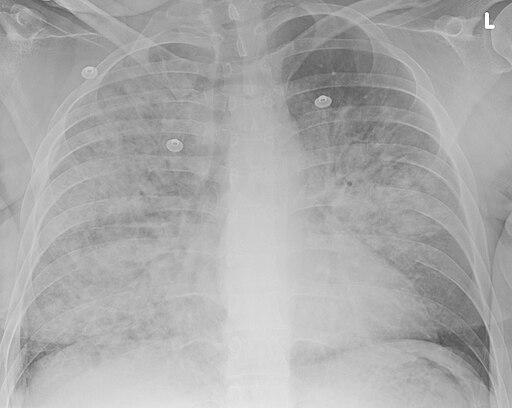

Aspiration pneumonia

Doc James, CC BY-SA 4.0, via Wikimedia Commons

A chest X-ray.